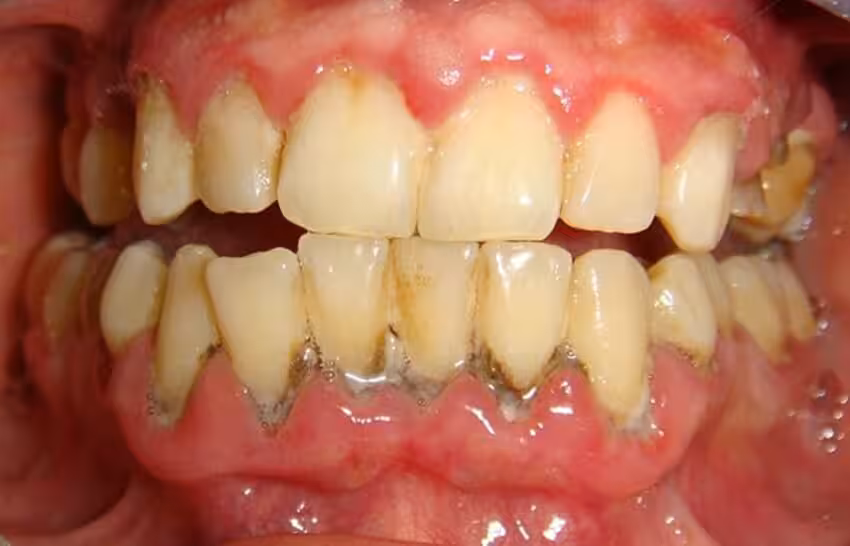

Cao răng có 2 loại gồm cao răng thường và cao răng huyết thanh:

• Cao răng thường: Cao răng thường hình thành phía trên đường viền nướu, có màu trắng đục hoặc vàng nhạt. Đối với những người thường xuyên hút thuốc lá sẽ có màu sẫm hơn. Cao răng thường nếu kéo dài sẽ gây viêm nướu, chảy máu chân răng,...

• Cao răng huyết thanh: Cao răng thường nếu không điều trị kịp thời, gây chảy máu nướu, máu ngấm vào mảng bám chuyển thành màu nâu đỏ gọi là cao răng huyết thanh. Cao răng huyết thanh xuất hiện trong khe hở (kẽ) giữa răng và đường viền nướu. Cao răng này thường có màu nâu hoặc răng đen và chứa nhiều vi khuẩn hơn, gây viêm nướu và đẩy nhanh tốc độ nhiễm trùng chân răng.

Cao răng dưới nướu có màu nâu hoặc đen và thường đi cùng tình trạng viêm nha chu.